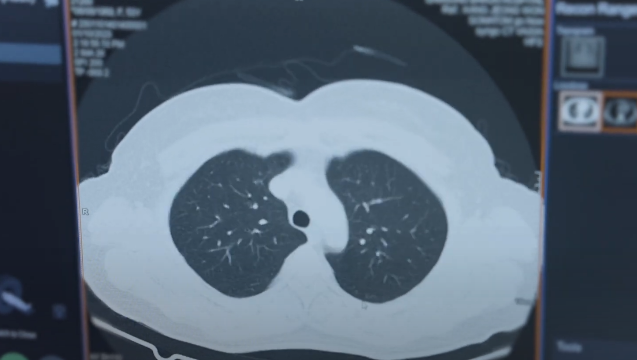

일반적으로 CT(Computed Tomography) 검사로 잘 알려져 있는 전산화 단층 영상검사는 X선이 인체를 회전하면서 방사선을 투과하여 얻은 영상 정보를 컴퓨터가 분석하여 인체를 횡단면 영상으로 보여주는 검사입니다.

CT 검사는 뇌 흉부 복부 척추 골반 뼈 등 우리 몸 전체의 종양이나 이상 병변을 외과적인 수술 없이 파악할 수 있으며 검사하는 동안 통증이 없는 비교적 안전한 검사로, 특히 일반 X선 검사와 달리 장기의 중첩되지 않는 단면 영상으로 세밀하게 병변을 확인할 수 있으며 3차원 영상으로 재구성도 가능하기 때문에 보다 많은 영상 정보로 진단할 수 있습니다.